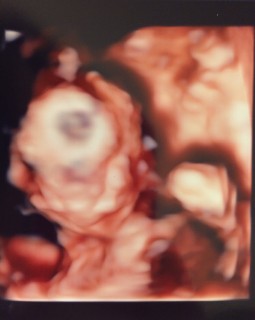

今回の検診で性別が判明♡おそらく女の子だろうとのこと(^^) 前回も今回も顔は見せてくれませんでした~(TT)恥ずかしがりやさんなのかな?笑 428gで順調とのことでした♪

400gくらいだそうです。順調に育っており、確実に女の子と言われました!先週くらいから胎動もはっきり感じるようになり、元気なんだなぁと実感できて嬉しさも増します。胃痛に苦しむ日々ですが、がんばろうと思いました!